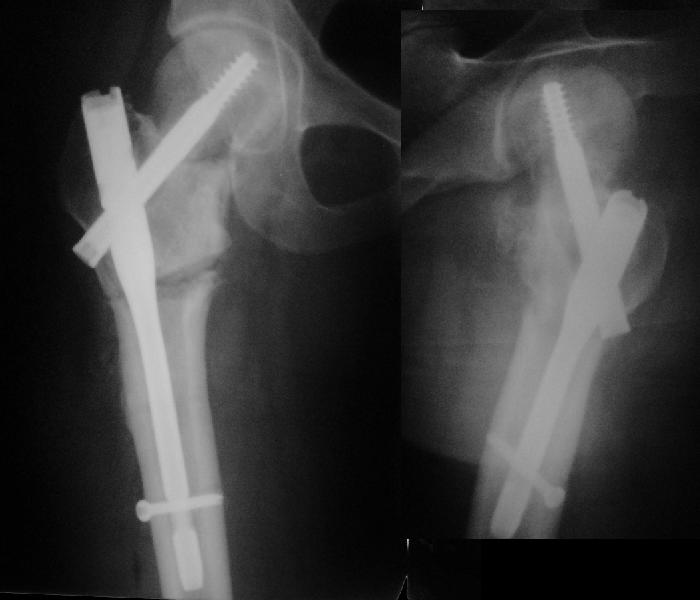

Учитывая возраст больного и качество кости, я однозначно за остеосинтез. Можно обойтись и без остеотомии, линия излома не вертикальная. Возможно с костной аутопластикой для стимуляции. Только отрепонировать хорошо, на представленных снимках, перелом недорепонирован, есть ротационное смещение. Плюс винт биомеханически введен не совсем удачно.

на представленных рентгенограммах прослеживается линия резорбции вокруг введенного винта, что свидетел ствует о нестабильности произведенного остеосинтеза ии отсутствии консолидации перелома. На мой взгляд нужно произвести ркт исследование и выполнить при отсутствии консолидации реостеосинтез с костной аутопластикой. При отсутствии сращения после данной операции остается ввариант с эндопротезированием. Выполнить репозицию несросшегося перелома закрытым способом на мой взгляд не совсем реально, открытая репозиция чревата аваскулярным некрозом. Выполнение вальгизирующей остеотомии считаю нецелесообразным так как это приведет к увеличению давления на головку (за счет натяжения мышц бедра )6 лишенную нормального кровотока приведет к ее коллабированию. С уважением Даниленко Олег.

Учитывая, что при первичном синтезе DHS репозиция, по всей видимости, была неадекватная, то открывая область перелома для репозии, можно получить аваскулярный некроз головки.

Согласен с Paul, что возможно удаление гвоздя DHS, аутокостное штифтование по ходу гвоздя, и дополнительная фиксация 3 мя компремирующими винтами, что позволит активизировать больного без внешней иммобилизации.

Уважаемый Александр! Что имеем? Судя по представленной Вами информации (Р-граммы и клиника), несмотря на крайне неудовлетворительное стояние отломков имеет место неполное сращение перелома. В противном случае никак не возможна ходьба с тростью, практически полное отсутствие болей, нет и асептического некроза. Отсюда и должны рассматриваться варианты дальнейшей тактики.Эндопротезирование, открытые репозиции, остеотомии вряд ли адекватны имеющейся ситуации.

Никто не обратил внимания, что конструкция-то вся "развинчена" - вывернулся винт из шеечного винта, пластина не прилегает к диафизу. Резорбция кости вокруг шеечного винта не позволит как-нибудь надежно синтезировать вальгизирующую остеотомию, а в случае неудачи сама остотомия осложнит последующее эндопротезирование. Поэтому, думаю, что лучшим вариантом будет синтез аутокостью + канюлированные винты (дабы избежать кокситной повязки).

Я бы ограничился вальгизацией без вмешательства в зону перелома шейки. Биология здесь, надо полагать, хорошая, необходимо только улучшить механическую составляющую.

В итоге что-то такое и сделали. Убрали DHS, остеотомия, синтезировали Affixus с небольшой вальгизацией. Снимки в приложении.

Похоже удалось провести шеечный винт мимо старого канала, и вальгус, вроде, удался. Только хороший-ли контакт фрагментов в зоне остеотомии? Действительно - жизнь покажет.